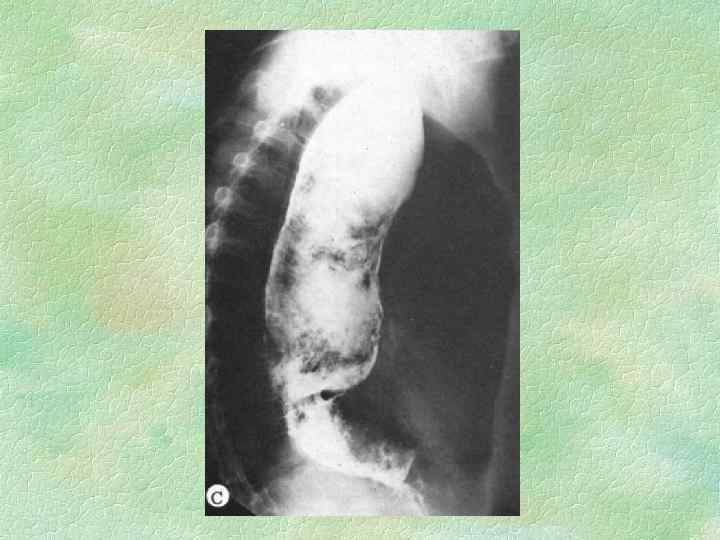

СТАДИИ КАРДИОСПАЗМА (Б. В. Петровский, 1962) I II IV непостоянный функциональный спазм без расширения пищевода постоянный спазм с незначительным расширением пищевода рубцовые изменения и органический стеноз с выраженным расширением пищевода резкий стеноз, удлинение и S-образная деформация пищевода